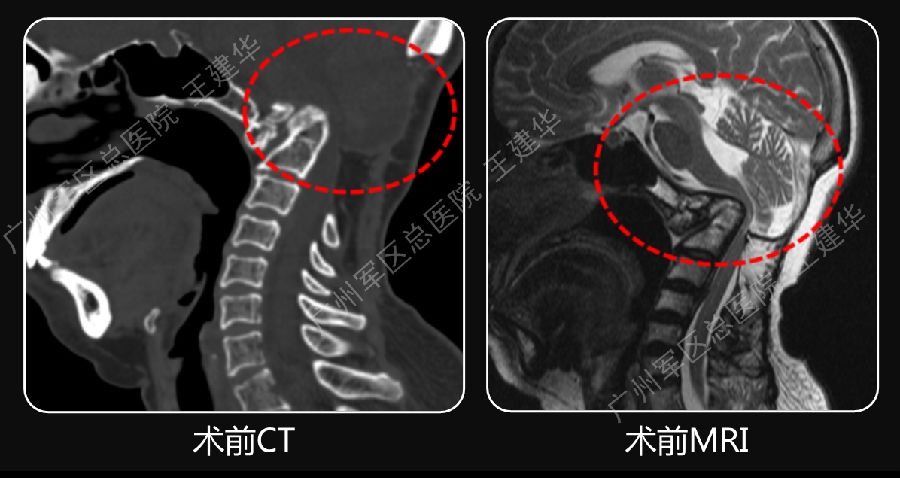

术前术后对比

病例2

术前诊断

手术前后对比

手术后CT显示,陷入枕骨大孔的齿突获得下拉复位

术后MRI发现,患者的颅底凹陷,脊髓空洞和Chiari畸形均获改善